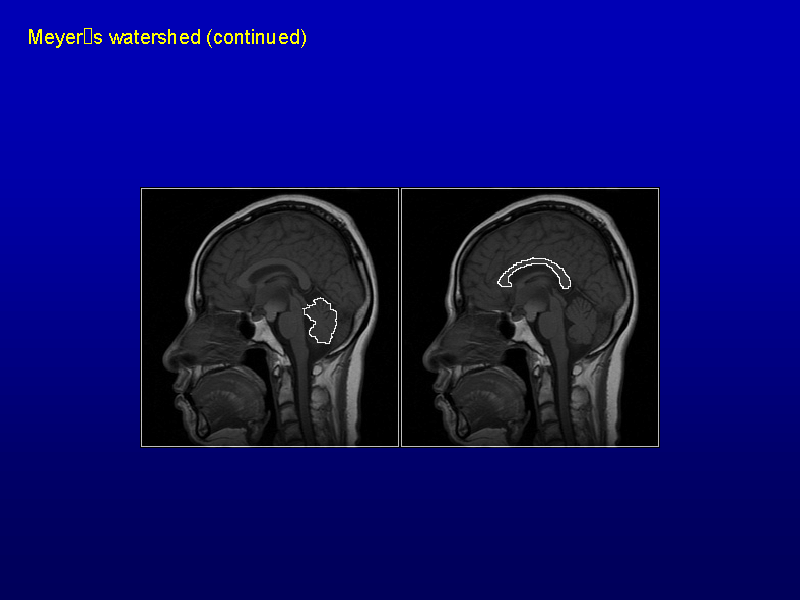

Slide 20 of 34